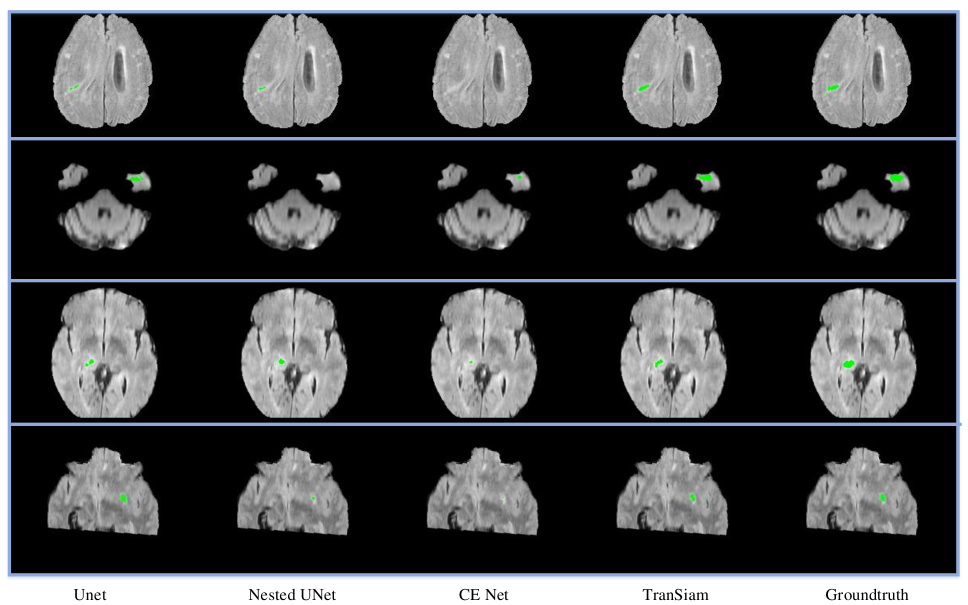

4.6 Visual analysis

We perform a visual analysis for our experimental results. It is worth noting that the validation set of brats 2019 and brats 2020 does not provide groundtruth. Therefore, we apply the brats 2020 training set for training our model, and select part of the brats 2019 training set as our validation set. On the validation set, we visualize the segmentation results of several classical networks, which is shown as Figure 4. We use green to mark whole tumor. As can be seen from Figure 4, although our TranSiam integrates the transformer, it can still segment small tumor. It means that we combine convolution with transformer is meaningful. It can alleviate the problem that the transformer loses detailed information. With the help of the transformer, TranSiam is even able to segment tumors that are not segmented by traditional CNNs. It means that our TranSiam fully combines the advantages of transformers and convolutions for multimodal medical image segmentation.